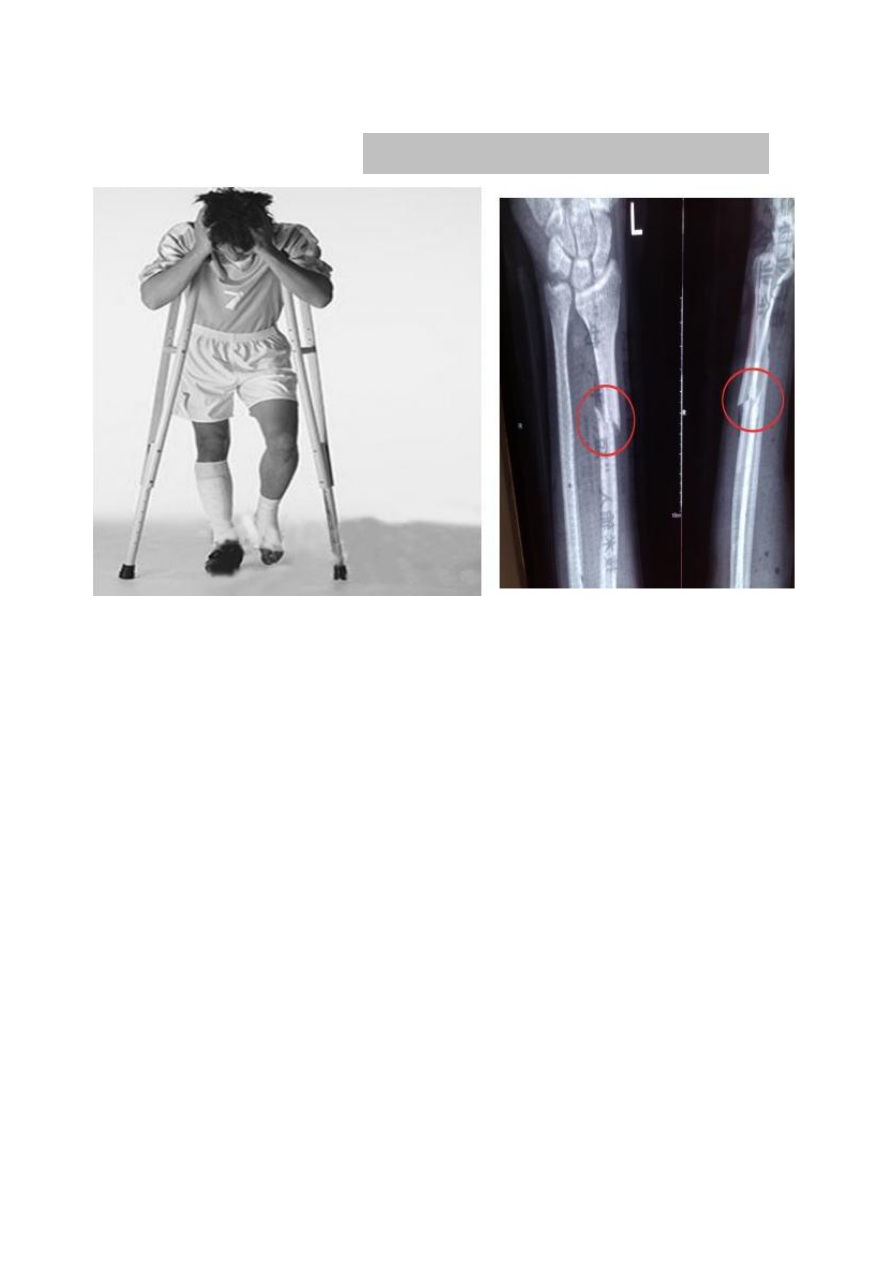

作,逐渐恢复肢体活动范围;下肢骨折者需借助拐杖或助行器,从“部分负重”开始,比

如先让患肢承担 10%-20%体重,再根据恢复情况逐步增加。此阶段需避免剧烈运动,防止骨

痂断裂。

可开展蹲起、上下楼梯等训练,逐步摆脱拐杖。对于运动员、体力劳动者等特殊人群,还

需进行专项功能训练,比如跑步、跳跃等,确保恢复到受伤前的运动水平。